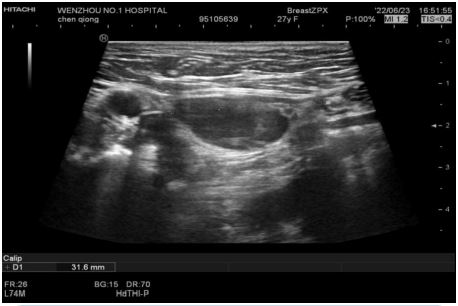

Figure 2: On the right inguinal area, a liquid dark area with a range of approximately 58×15×32 mm was observed between the subcutaneous fat layer and muscle layer.